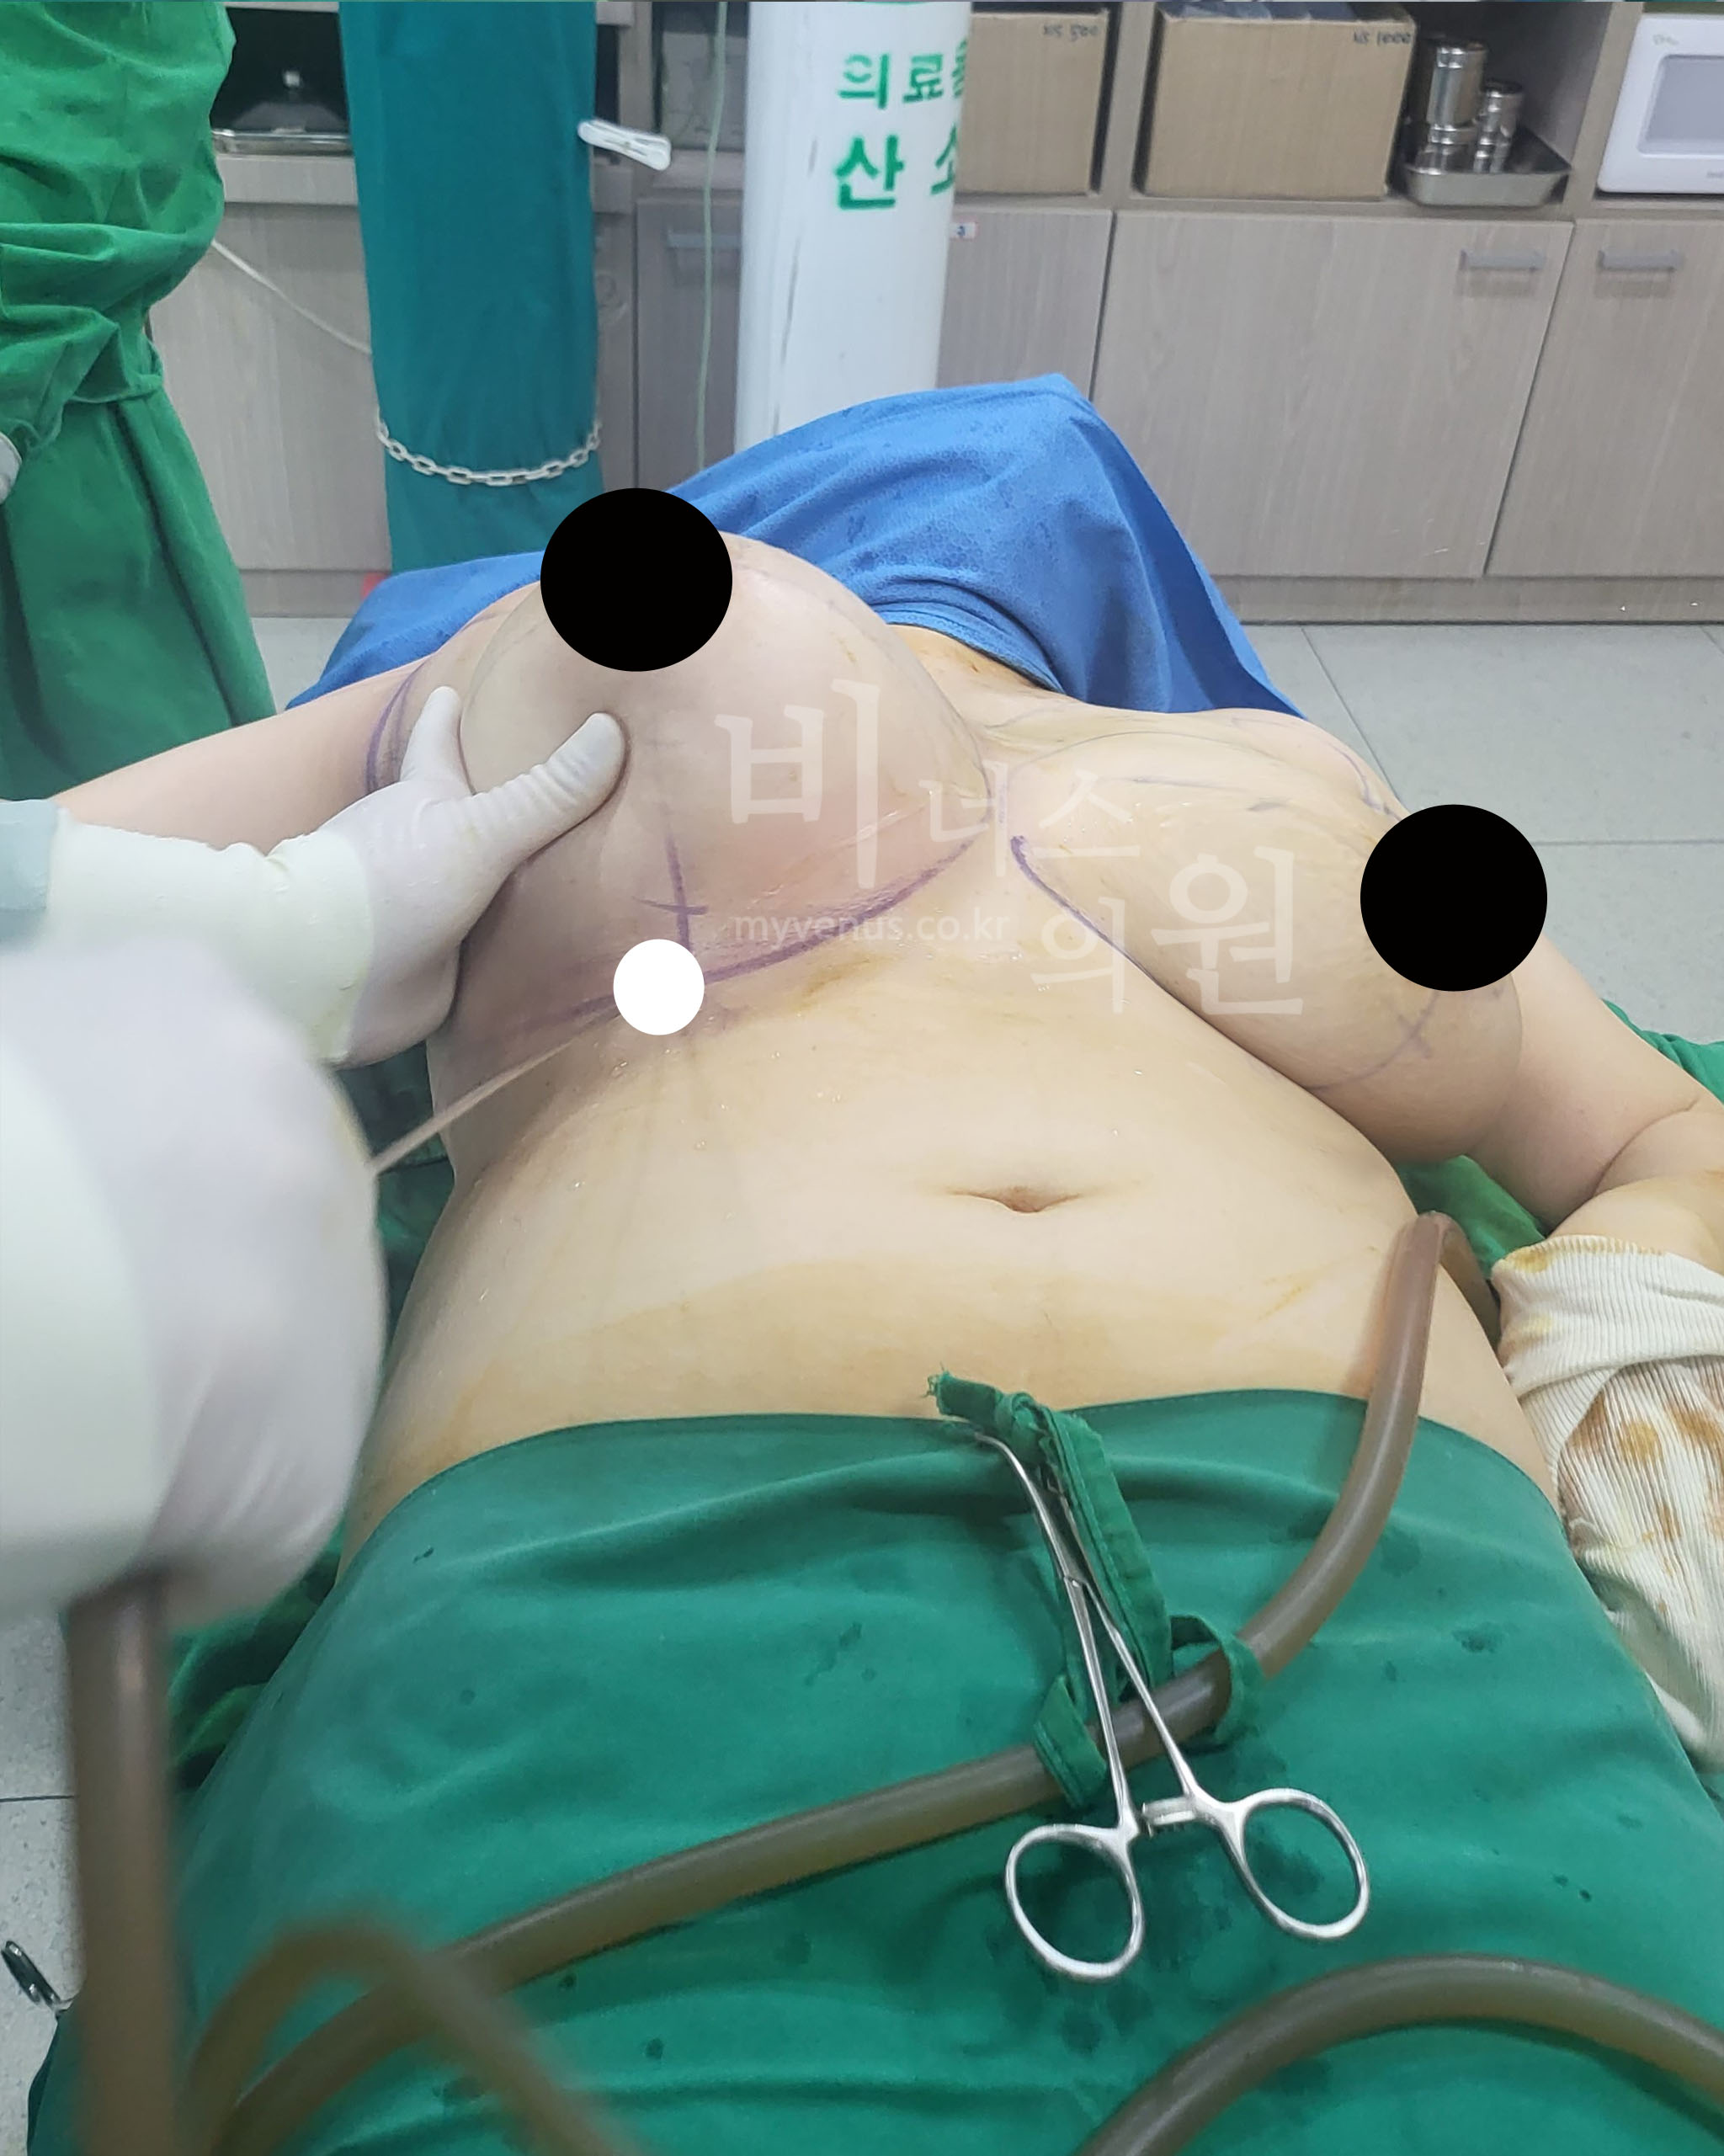

안전하게 예뻐지는 투메슨트 지방흡입

안전한 가슴축소 지방흡입

투메슨트 용액을 주입하고 있는 모습

사이즈 감소가 확실한 가슴지방흡입

양쪽 가슴이 빵빵하게 부풀려진 모습

안전한 투메슨트 가슴축소 지방흡입은 용액을 지방조직에 주입하고 지방세포가 부풀어지면 지방 조직을 흡입하는 방법이에요. 지방조직이 혈관을 수축시키고 동시에 부풀려진 지방을 흡입하기 때문에 출혈이 적어요. 수술 후에도 국소마취제가 지방층에 남아있어 추가적인 진통제 주사 없이도 수술 후 통증이 일반적으로 없어요.

최소의 절개를 내어 가슴지방흡입하는 모습